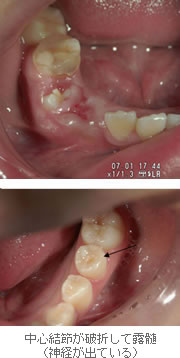

突起の中には神経が通っているため、折れてしまうと露髄(神経が出ること)してしまいます。突起は咬合面にあるため、咀嚼や歯ぎしりが原因で折れてしまうことも珍しくありません。

引用:日本小児歯科学会